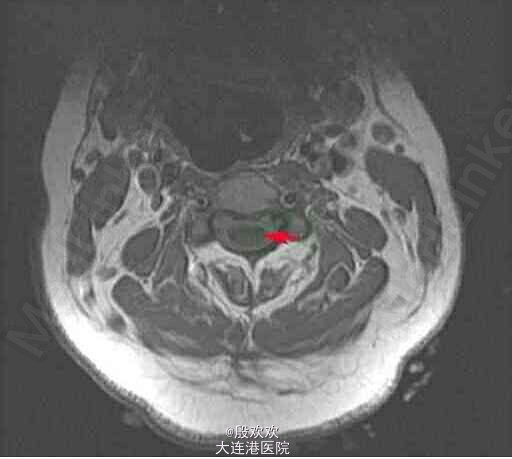

患者,女,51岁,因“右上肢无力萎缩10+年,双上肢麻木5年”入院。患者10+年前感右上肢力弱,逐渐加重,并发现右手肌肉渐萎缩。后双上肢麻木。

查体:生命体征平稳,双上肢皮肤粗糙。专科查体:神清,语利,双侧颈5-胸4水平痛温觉减退。双下肢肌张力稍高,右手骨间肌肉萎缩。双侧腹壁反射消失,双肱二头肌肌腱、肱三头肌肌腱、桡骨膜反射减低,双侧膝反射、踝反射明显增高。 辅助检查:头+颈椎+胸椎MRI:charis畸形并脊髓空洞症。

诊断:脊髓空洞症并小脑扁桃体下疝畸形:charis I型畸形。治疗:给于给于维生素B、ATP、肌苷等营养神经及康复治疗。